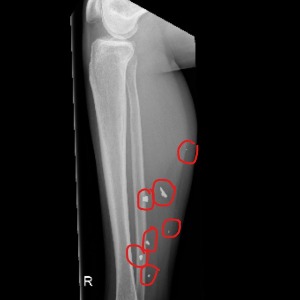

In memory of October 18th, 1992: the day I was wounded in a mortar shell explosion that left numerous shrapnel in my legs, I CHOOSE STRENTGH and RESILIENCE.